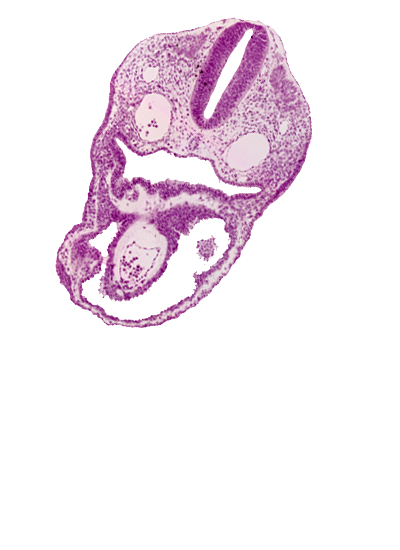

Carnegie Embryo #8943 | Location: 03-04-01

Keywords: aortic sac, dermatomyotome 2 (O-2) , dorsal aorta, notochord, pericardial cavity, pharyngeal pouch 3, pharynx, rhombencephalon (Rh. D)

Source: The Virtual Human Embryo.